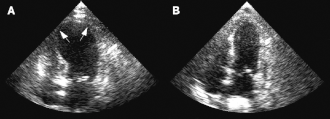

Durante el curso de la evaluación del paciente, se observa con frecuencia un abultamiento de la punta del ventrículo izquierdo con una hipercontractilidad de la base del ventrículo izquierdo, característica que le dio al síndrome el nombre de takotsubo (蛸壺, «trampa de pulpos» en Japón, donde fue descrita por primera vez).[6]